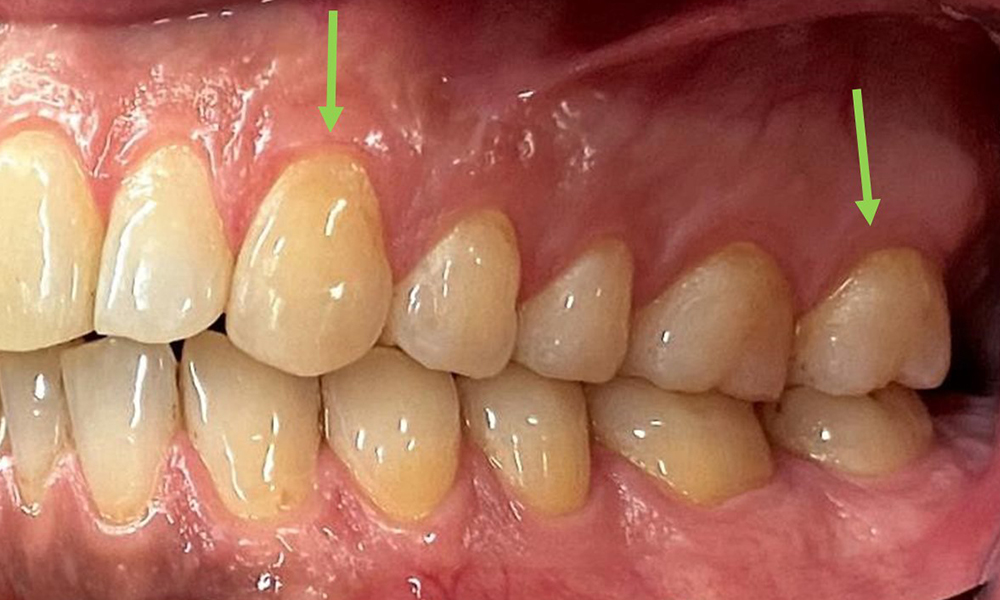

Frontalansicht

Abb. 2 Frontalansicht, © Dr. R. Krapf

Extraoral sind keine pathologischen Befunde festzustellen, intraoral zeigen sich bei der Frontalansicht im Bereich der keratinisierten Gingiva und am Übergang zur beweglichen Schleimhaut bräunlicheVerfärbungen (Abb. 2), welche auf den Nikotingenuss zurückzuführen sind. Am Gaumenbereich zeigen sich insbesondere im Bereich Oberkiefermolaren palatinal weißliche Schleimhautveränderungen, die ein Hinweis auf einen erhöhten Verhornungsgrad sind und ebenso auf den Nikotingenuss zurückzuführen sind. Die Zunge ist mit einem weiß-bräunlichen abwischbaren Belag versehen.

Nahaufnahme der Zähne

Abb. 5: Nahaufnahme der Zähne 45-47. Grüne Pfeile zeigen Attritionen und Erosionen im Bereich der bukkalen Höcker mit partiellem Schmelzverlust, © Dr. R. Krapf